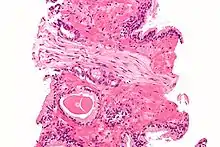

A diagnosis of prostate cancer requires a biopsy of the prostate. Prostate biopsies are typically taken by a needle passing through the rectum or perineum, guided by transrectal ultrasound imaging, magnetic resonance imaging (MRI), or a combination of the two.[22][20] Ten to twelve samples are taken from several regions of the prostate to improve the chances of finding any tumors.[20] Biopsies are examined under a microscope by a pathologist, who determines the type and extent of cancerous cells present. Cancers are first classified based on their appearance under a microscope. Over 95% of prostate cancers are classified as adenocarcinomas (resembling gland tissue), with the rest largely squamous-cell carcinoma (resembling squamous cells, a type of epithelial cell) and transitional cell carcinoma (resembling transitional cells).[23]

Next tumor samples are graded based on how much the tumor tissue differs from normal prostate tissue; the more different the tumor appears, the faster the tumor is likely to grow. The Gleason grading system is commonly used, where the pathologist assigns a number from 1 (similar to prostate tissue) to 5 (least similar) for the most common pattern observed under the microscope, then does the same for the second-most common pattern. The sum of these two numbers is the Gleason score.[23] The total scores of 2 through 5 are no longer commonly used in practice, making the lowest score 6, and the highest score 10. Scores are commonly grouped into Gleason grade groups: a score of 6 or lower is Gleason grade group 1; a score of 7 with the first number (from the most common pattern) 3 and the second number 4 is grade group 2; the reverse – first number 4, second number 3 – is grade group 3; a score of 8 is grade group 4; a score of 9 or 10 is grade group 5.[23] Higher Gleason scores and higher grade groups represent cancer cases likely to be more aggressive with worse prognosis.[23]